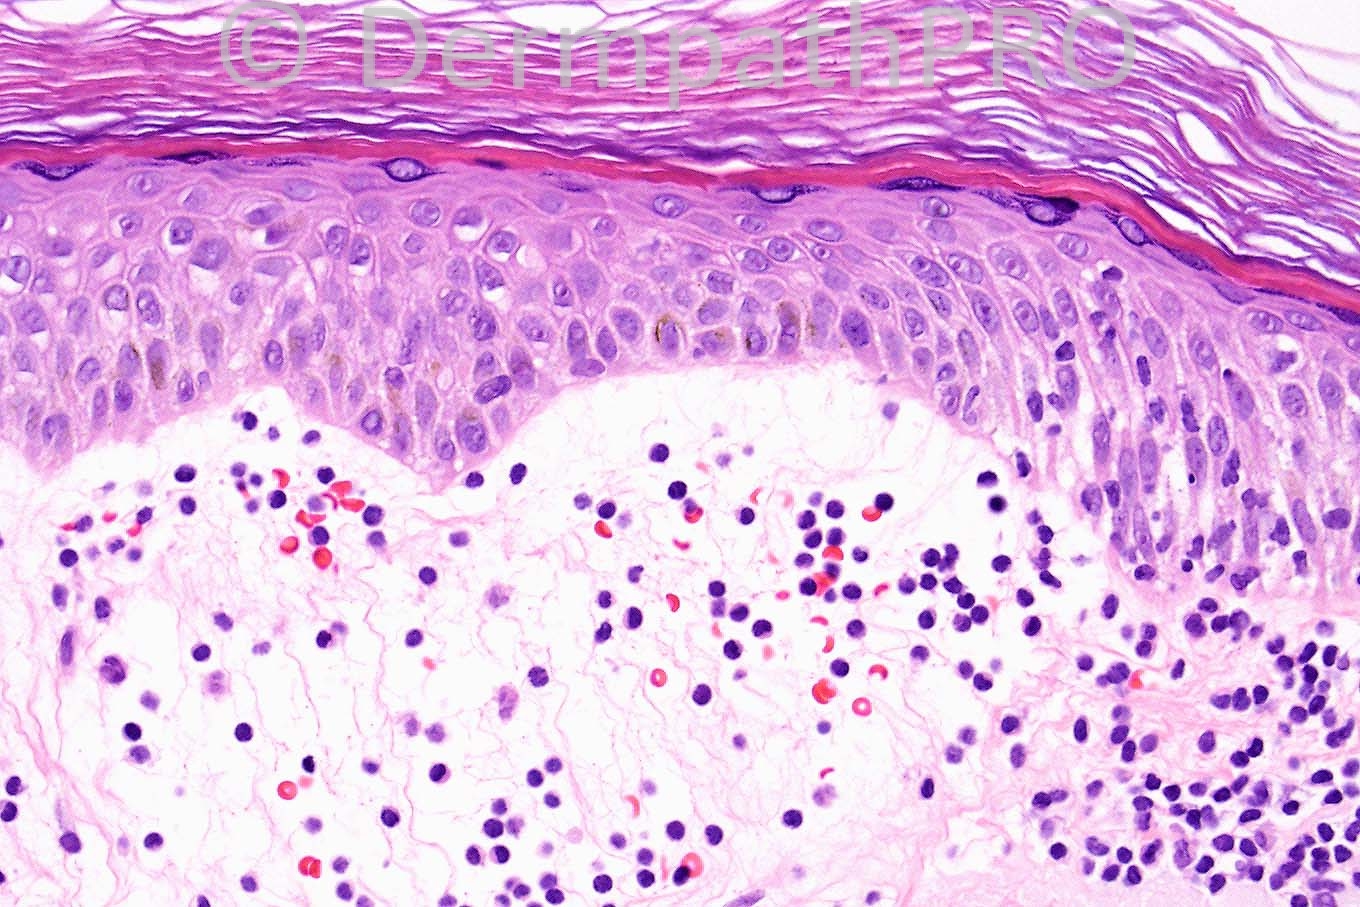

Female 19 years, edematous papules on face.